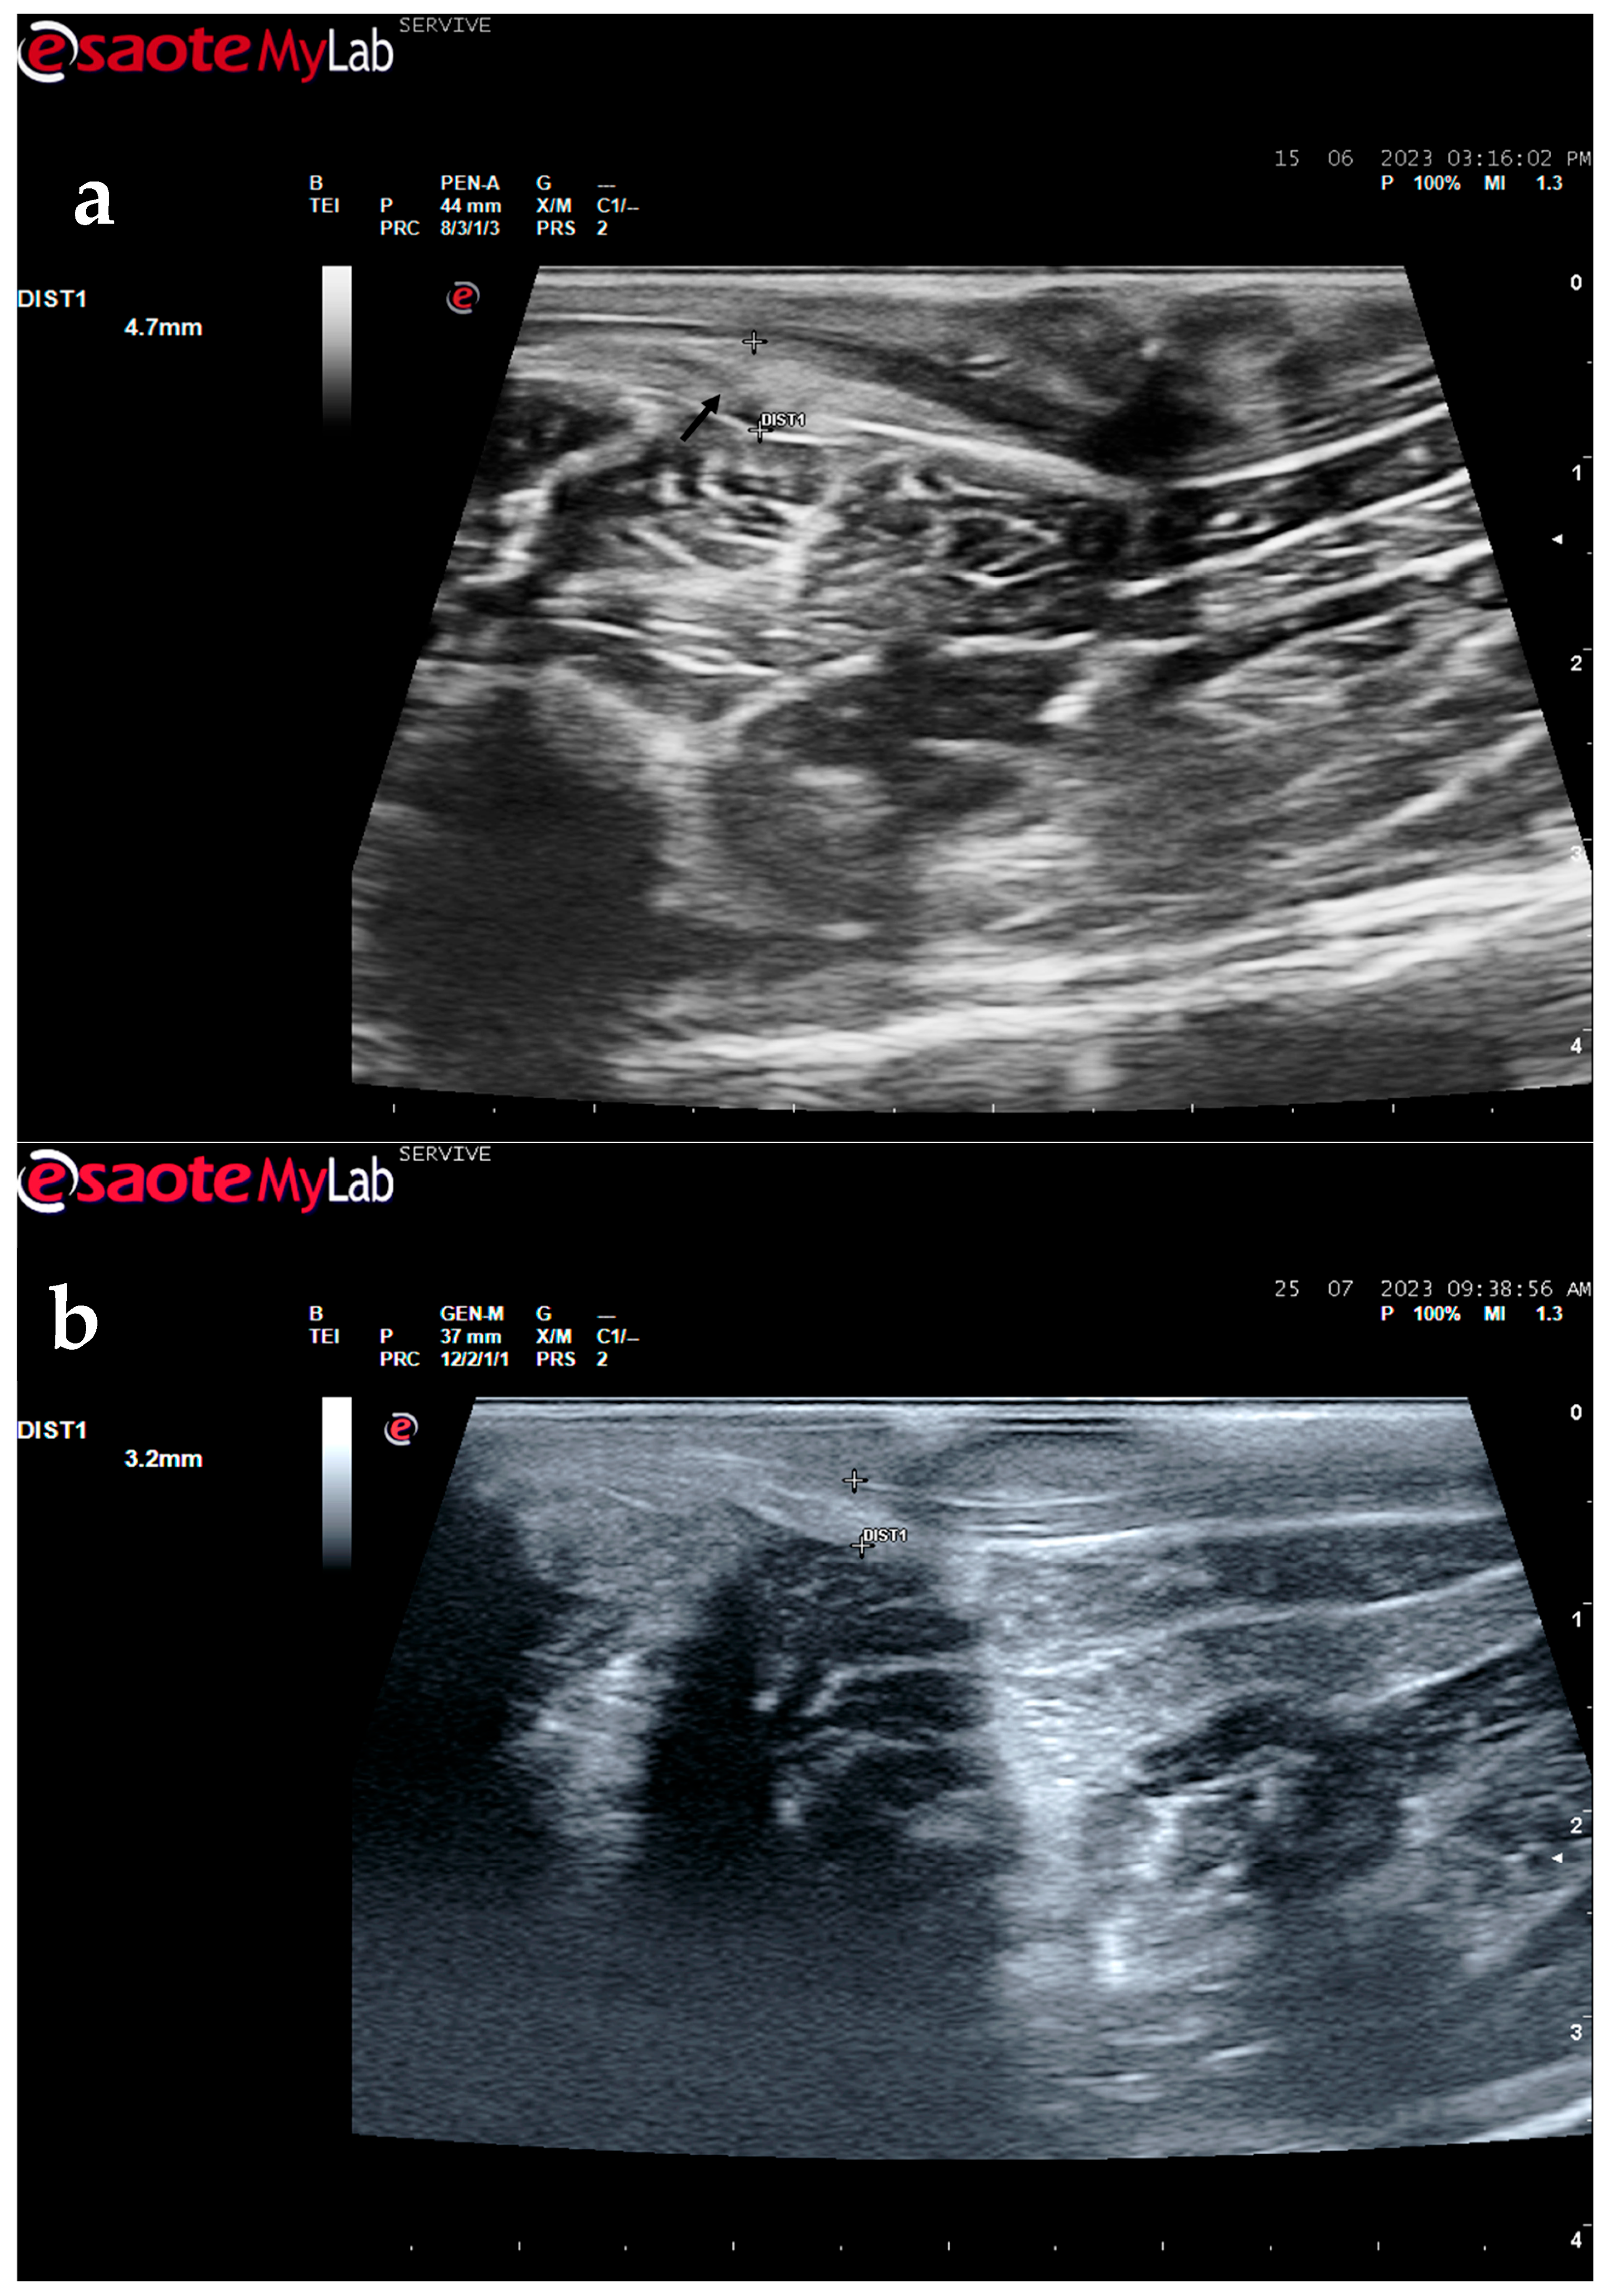

The described technique allows an easy follow-up of the progression of nerve regeneration over time after the induction of a lesion in a controlled surgical environment. For example, after the application of a tube guide, in which the nerve tops of a transected nerve are sutured to the ends of the tube, leaving a gap to be filled inside the biomaterial, immediately after surgery, it is possible to identify the tube guide and the nerve tops inside of it by ultrasound (Figure 9). The tube guide appears as a hyperechogenic structure, at the ends of which the nerve tops are observed (Figure 9a), allowing the measurement of the created gap and its evaluation and measurement over time until the total closure and reconnection of the nerve ends (Figure 9b). In the same way, after the application of end-to-end sutures, in which the ends of the transected nerve are coapted and sutured in order to guarantee their reconnection and anatomical continuity, it is possible to observe the nerve continuity (Figure 10), but at early timepoints after the injury, a small hypoechoic gap appears as a result of the transection. An edema, in association with the inflammatory infiltration resulting from the degenerative phase after the nerve injury, promotes a transient increase in the diameter of the nerve (Figure 10a) that ends up disappearing over time (Figure 10b). In addition to the increase in diameter, due to interstitial edema, the nerve also appears with an increased hyperechogenic appearance. The main advantage of applying ultrasound in the monitoring of nerve regeneration will be to allow the observation of macroscopic morphological changes in the nerve over time, namely changes in its anatomical continuity, in the dimensions of the created nerve gaps, in their diameter, and in the presence or absence of edema and inflammatory infiltrate. Microscopic changes such as endoneurial microvascular degeneration, demyelination/remyelination, and axonal density and reorganization should be later confirmed by more sensitive histomorphometric techniques such as nerve stereology. At the same time, the functional translation of the regenerative process can be evaluated in parallel through functional and behavioral tests, determination of nervous conductivity, and biomechanical and kinematic gait studies.

Figure 9.

Ultrasound image of the left peroneal nerve in a sheep subjected to a transection lesion followed by the application of a tube guide. (a) After 1 week, it is possible to observe the tube guide as a hyperechogenic tubular structure (black arrows) at the ends of which the ends of the transected nerve are inserted (white arrows). DIST1 represents the length of the gap left between the two nerve ends. (b) After 3 months, the tube continues to be perfectly visible (black arrows), and the nerve is introduced into its lumen (white arrows); but now, instead of the gap between the nerve tops, an anatomical continuity of the nerve is observed along the entire tubular lumen (beige arrow), indicating a nerve reconnection. In the center of the tubular lumen, a hypoechoic space not filled by nervous tissue is also observed (brown arrow), indicating that the regenerating nerve has not yet occupied all the available space inside the tube guide. DIST1 represents the nerve diameter, and DIST2 represents the inner diameter of the tube guide.

Figure 10.

Ultrasound image of the left peroneal nerve in a sheep subjected to a transection lesion followed by the application of an end-to-end suture. (a) After 1 week, it is possible to observe that the nerve continuity is still interrupted by a gap between the two nerve tops that have not yet fully reconnected (black arrow). DIST1 represents the nerve diameter, which is enlarged and with an increased hyperechogenic appearance due to interstitial edema and inflammatory infiltrate. (b) After 3 months, the nerve already presents an anatomical continuity, it is less hyperechogenic, and its diameter has decreased considerably (DIST1).